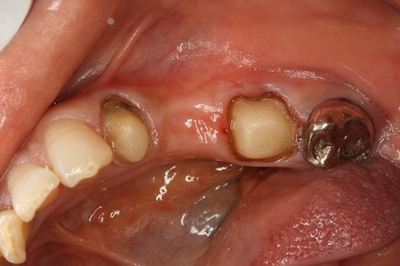

実際のおくちです。(ミラー像)